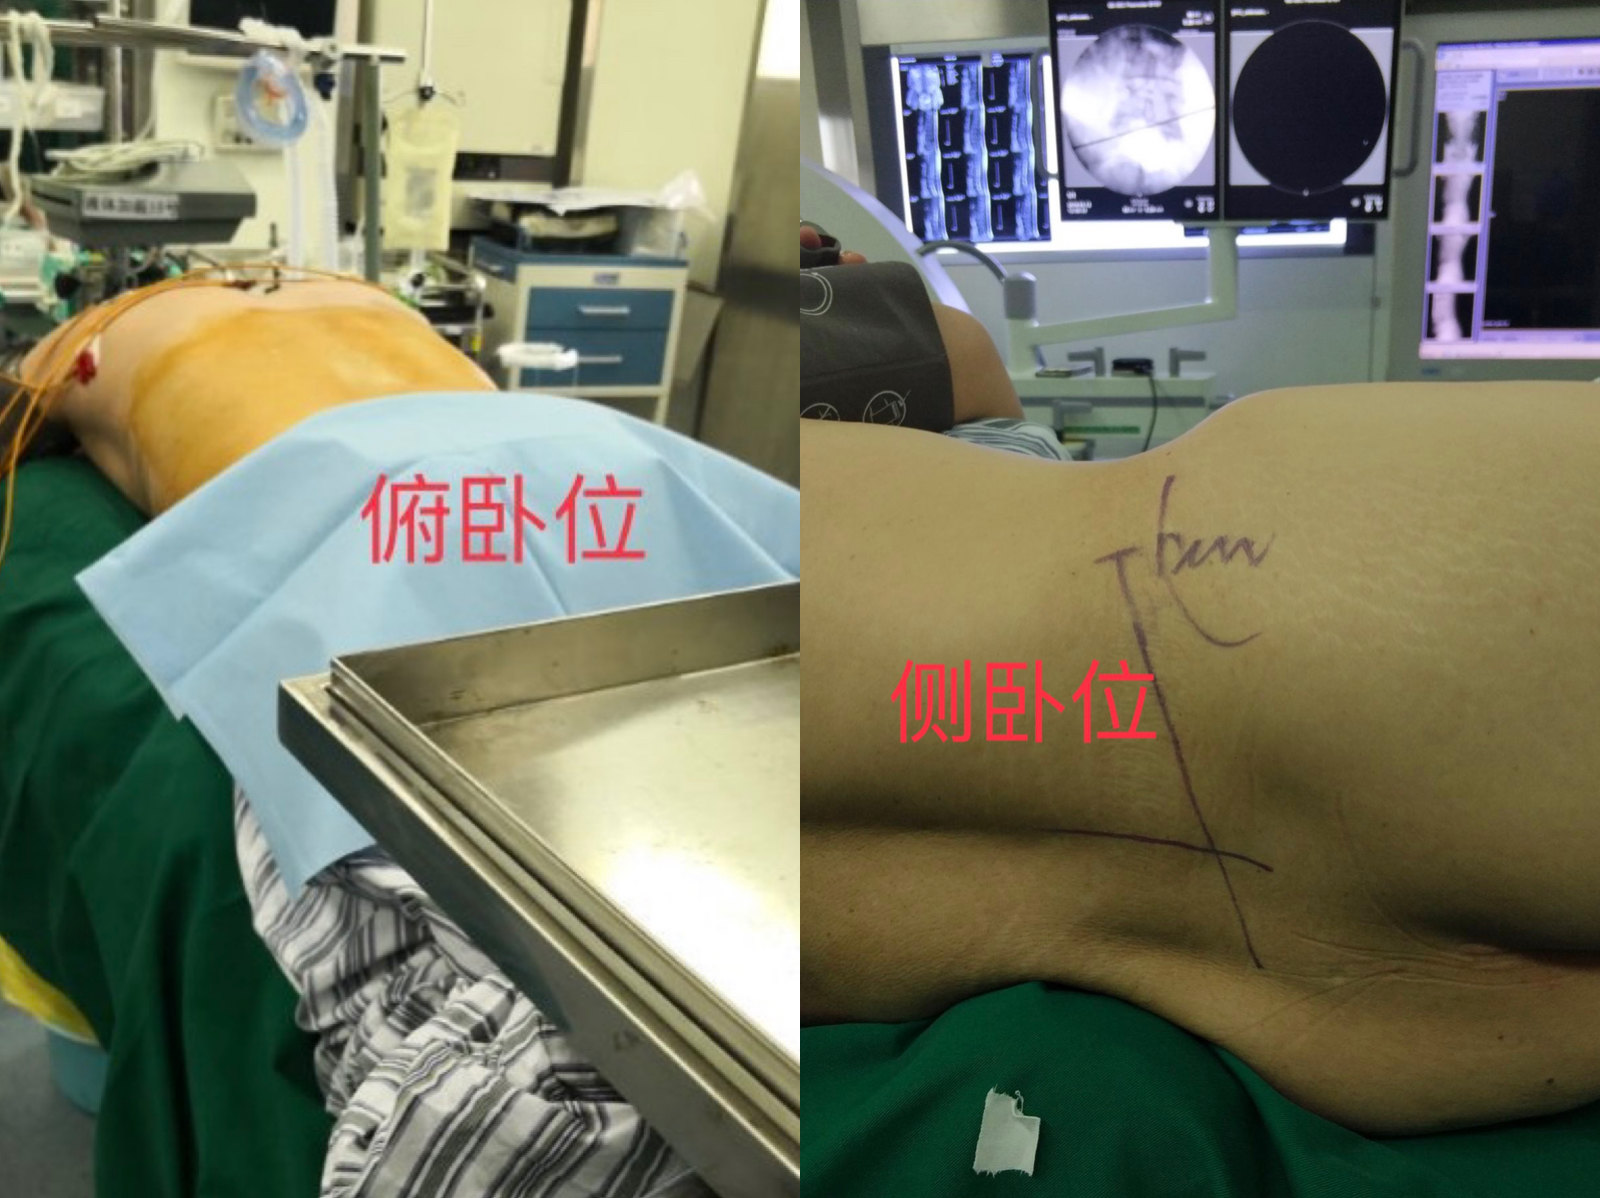

手术体位摆放

进入手术室后第一件事是摆放标准手术体位,这个过程需要患者一起配合。目前常用的是两种体位,分别为俯卧位(趴着)和侧卧位(侧躺)。两种方式均可顺利完成手术,主要取决于医生的个人习惯,没有孰优孰劣之分。